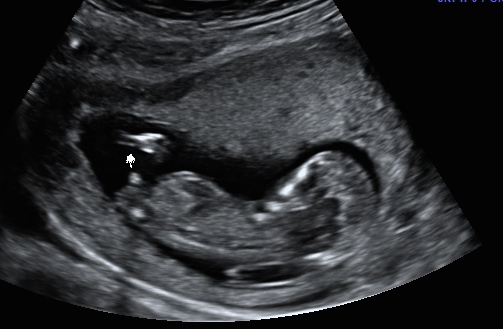

That is a very obvious boy nub! I will be shocked if that's not a boy.

I'd be pretty surprised if you didn't hear blue! That's very boyish.

I see all boy there!

All boy 100%!!